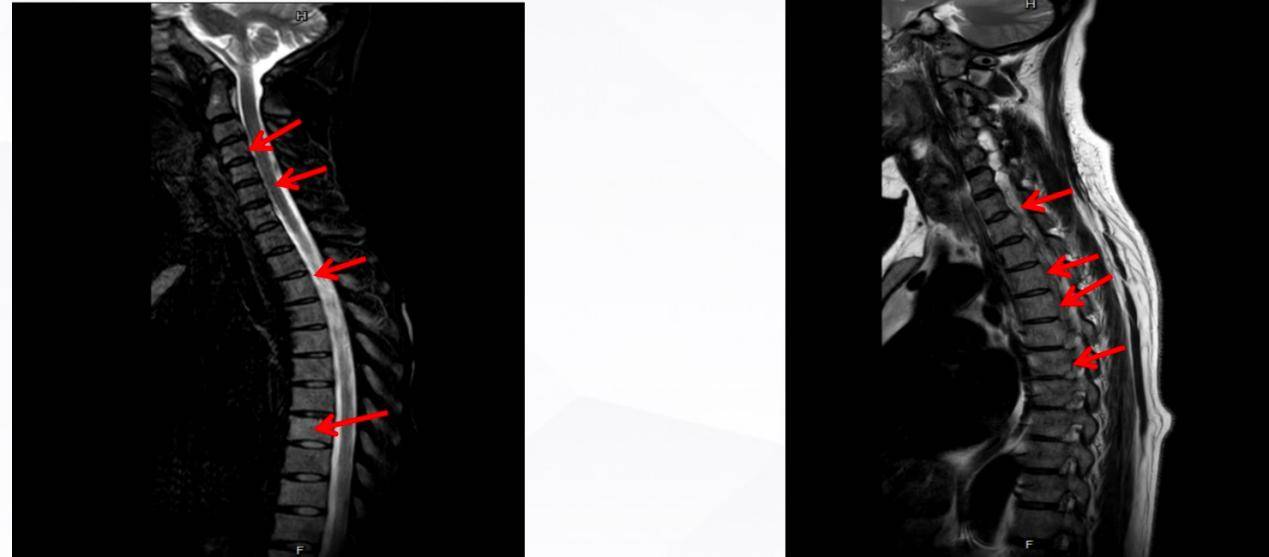

影像学检查:该患者全身多骨弥漫斑片状骨质破坏伴部分病灶代谢稍增高(明显者位于胸骨,SUVmax约3.9),左侧胫骨上段髓腔病灶,均考虑多MM可能大,请结合病理除外其他;脊柱退行性变;双侧筛窦、上颌窦炎;左侧乳突炎。双侧颈部淋巴结反应性改变可能;颅骨、颈胸腰椎椎体及附件、骶椎内多发异常信号,考虑MM可能,请结合临床;C3/4、C4/5椎间盘轻度向后突出;

检查所示双侧肱骨、双侧肩胛骨、双侧肋骨、胸骨、胸腰椎椎体及附件、骶椎、骨盆诸骨、双侧股骨上段内多发斑片状低密度影,部分骨皮质不连续,考虑MM可能,请结合临床及实验室检查;